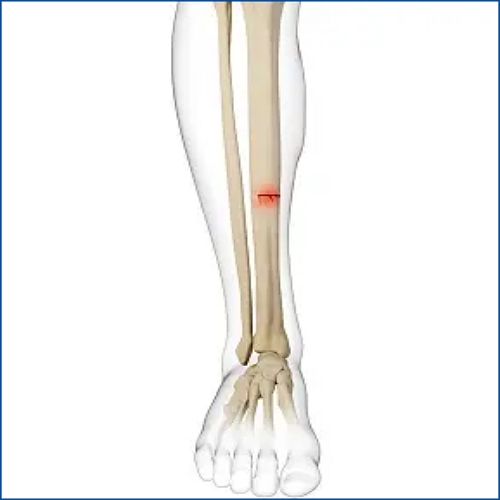

정강이 피로골절: 식별, 예방, 치료

정강이 피로골절은 하지의 스트레스가 많은 활동으로 인해 정강이(경골)에 발생하는 작은 균열입니다. 장기간 달리기, 걷기, 뛰기 또는 무거운 물건을 자주 드는 활동으로 인해 발생할 수 있으며, 특히 운동 선수, 군인, 댄서 등에서 흔히 발생합니다. 이러한 골절은 초기에 증상이 경미하여 간과하기 쉽지만, 적절한 치료 없이는 증상이 악화될 수 있습니다.

정강이 피로골절 증상

정강이 피로골절의 주요 증상은 다음과 같습니다.

- 통증: 초기에는 운동 중에만 통증이 발생할 수 있으나, 점차 휴식 시에도 지속될 수 있습니다. 통증은 보통 정강이의 내측 중앙 부근에서 더 심하게 느껴집니다.

- 부기: 부상 부위 주변이 붓는 경우가 많습니다.

- 압통: 골절 부위를 가볍게 눌렀을 때 통증이 느껴지는 것을 의미합니다.

- 활동 시 악화되는 통증: 활동을 시작할 때보다 활동 후에 통증이 더 심해지는 경향이 있습니다.